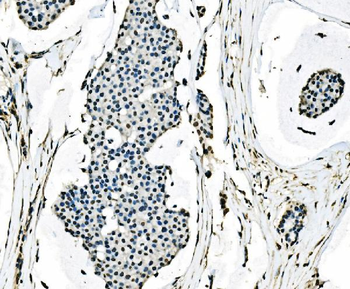

- PPM1D Rabbit Polyclonal Antibody [orb704535]Featured

IF, IHC-Fr, IHC-P

Human, Mouse, Rat

Mouse, Rat

Rabbit

Polyclonal

Unconjugated

100 μl, 50 μl, 200 μl - HSC70 Mouse Monoclonal Antibody [orb704174]Featured